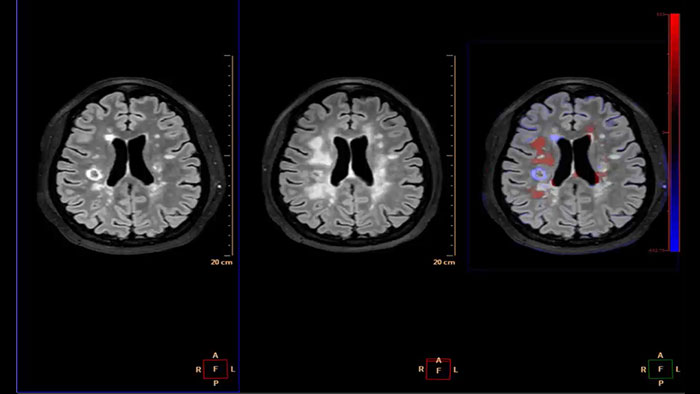

Reviewing brain tissue perfusion viability

Provides physicians with supporting information for the evaluation of stroke, or assessment and follow-up of brain tumors. The application supports the analysis of T2* Perfusion studies to generate parametric data including TTP, MTT or Tmax.

Generates qualitative and quantitative information about changes in image intensity over time. The application calculates and displays quantitative color maps of cerebral blood flow (CBF), cerebral blood volume (CBV), mean transit time (MTT) and time-to-peak (TTP), and provides summary maps which may help physicians in determining areas of reduced cerebral blood flow compared to the contra lateral hemisphere.

Determine areas of reduced cerebral blood flow as compared to the contralateral hemisphere